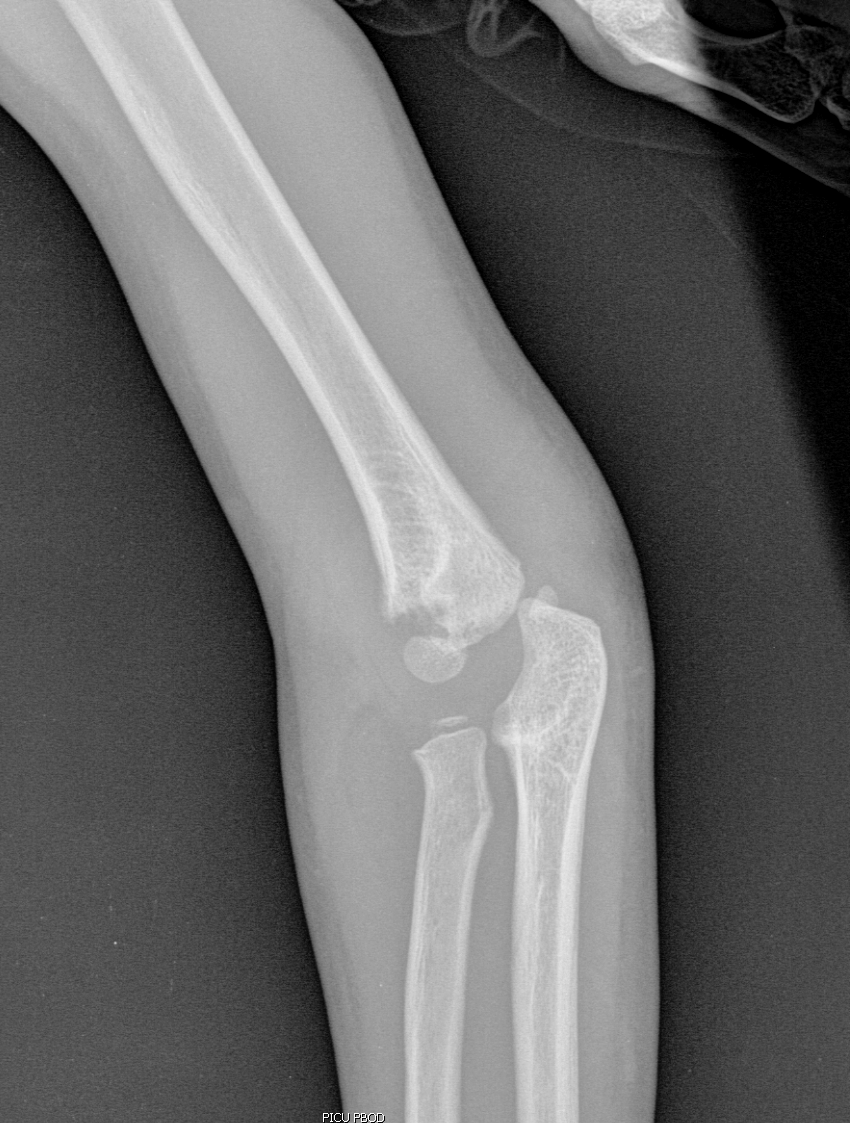

Info Images Findings Impression Reco/Acuity Case Images View Images / Launch Visage Case Notes History 2-month-old presents with decreased right arm movement, increased fussiness, and increased sleepiness for 2 days. Suspected non-accidental trauma. Exam Skeletal survey Prior Study none Dicom View Reference Material

Section 1 Submit Findings CB1550 Findings Skeletal Survey - Technique Check Skull AP/Lat Yes No Cervical and Thoracolumbar spine Yes No Chest X-Ray Yes No Ribs – Left/Right Oblique Yes No Abdominal X-Ray Yes No Pelvis with both hips Yes No Bilateral Humerus, Forearm, Hand Yes No Bilateral Femur, Tibia/fibula, feet Yes No Any additional lateral views of the extremities Yes No The exam is over or under penetrated. Yes No The exam may or may not be limited by overlying structures or soft tissues, body habitus, patient positioning, support devices, or motion. Yes No The area of concern is indicated by the patient, technologist, or care provider. Yes No The area of concern is included on the exam. Yes No Soft Tissues There is soft tissue swelling, indistinctness of fat/muscle planes, gas, or laceration in the area of clinical concern. Yes No There is an effusion, fat pad displacement, or fat fluid level. Yes No There is a radiodense or lucent foreign body. Yes No There are other densities, calcifications, post-surgical changes, or support devices in the soft tissues. Yes No Any support lines/tubes. Yes No Bone There is a break or interruption of the continuity of the cortical or cancellous bone. Yes No There is overriding of the trabeculae with apparent sclerosis. Yes No There is displacement of a fracture fragment. Yes No There is bowing of the bone in addition to the fracture at the apex of the bowed bone concerning for the greenstick. Yes No There is a spiral fracture of the leg concerning for toddler’s fracture. Yes No There is abnormal angulation or bulging of the cortical surface relative to the normal cortex which could be from a buckle or torus fracture. Yes No There is a displaced fragment which may be from avulsion by a tendon, ligament, or joint capsule or from a comminuted or other fracture. Yes No The stress trabeculae or other trabeculae of the cancellous bone are interrupted or otherwise abnormal. Yes No There is subperiosteal or endosteal reaction which could indicate a healing or subacute fracture or other abnormality. Yes No There is hard/soft callus formation. Yes No There is remodeling of the bone. Yes No There is a corner fracture or metaphyseal lesion that could be from nonaccidental trauma. Yes No There are multiple fractures of different ages. Yes No There are vertebral body/spinous process fractures. Yes No There are rib fractures. Location - posterior or lateral. Yes No There is scapular/sternal fracture. Yes No There are fractures of the digits. Yes No There are wormian bones. Yes No There are intrasutural bones. Yes No There is metaphyseal abnormality (lucencies, increased density, erosion) which may be from something other than injury such as stress, metabolic disease (e.g. rickets with loss or distortion of the zone of the provisional calcification), neoplasm (e.g. leukemia), heavy metals, inflammation, or infection. Yes No There are metaphyseal spurs. Yes No There are bony deformities involving multiple bones. Yes No The bones are gracile. Yes No There are non-healing fractures. Yes No There is/are focal or multifocal lytic/lucent, blastic/sclerotic or mixed density lesion(s) or other abnormality. Yes No Overall bone density is increased or decreased with or without thinning or thickening of the cortical or cancellous bone. Yes No Growth plates, ossification centers, apophyses The growth plate(s) is/are abnormal. Yes No There is widening of the physis from a fracture with or without displacement of the epiphysis (Salter-Harris I). Yes No There is a fracture through the physis which then extends into the metaphysis with or without angulation or displacement (S-H II). Yes No There is a fracture through the physis which then extends into the epiphysis and is intra-articular, with or without angulation or displacement (S-H III). Yes No There is a fracture through the metaphysis, physis, and epiphysis which extends into the joint space with or without angulation or displacement (S-H IV). Yes No There is narrowing of the physis from a compression fracture (S-H V). Yes No The apophysis, epicondyle, secondary ossification center, or accessory ossicle is displaced or otherwise abnormal. Yes No The ossification centers are underdeveloped. Yes No Joints and alignment There is an effusion, fat pad displacement, or fat fluid level. Yes No The epiphysis or subchondral bone is fractured, interrupted, flattened, compressed, impacted, displaced, or otherwise abnormal. Yes No There is an intra-articular loose body or chondrocalcinosis. Yes No The joint is widened, narrowed, dislocated, malaligned, or incongruent. Yes No There is pseudoarthrosis. Yes No Other findings There are developmental changes or other anatomic variants or other existing conditions that may or may not be contributing to symptoms which can or should be further evaluated non-emergently or are otherwise incidental. Yes No The remainder of the exam is abnormal for age. Yes No The lungs show focal airspace opacity. Yes No There is pneumothorax. Yes No There is organomegaly. Yes No There is intra-abdominal calcification. Yes No There is displacement of the bowel loops. Yes No There is free intraperitoneal air. Yes No The bowel loops are dilated/obstructed. Yes No There is paraspinal soft tissue abnormality. Yes No